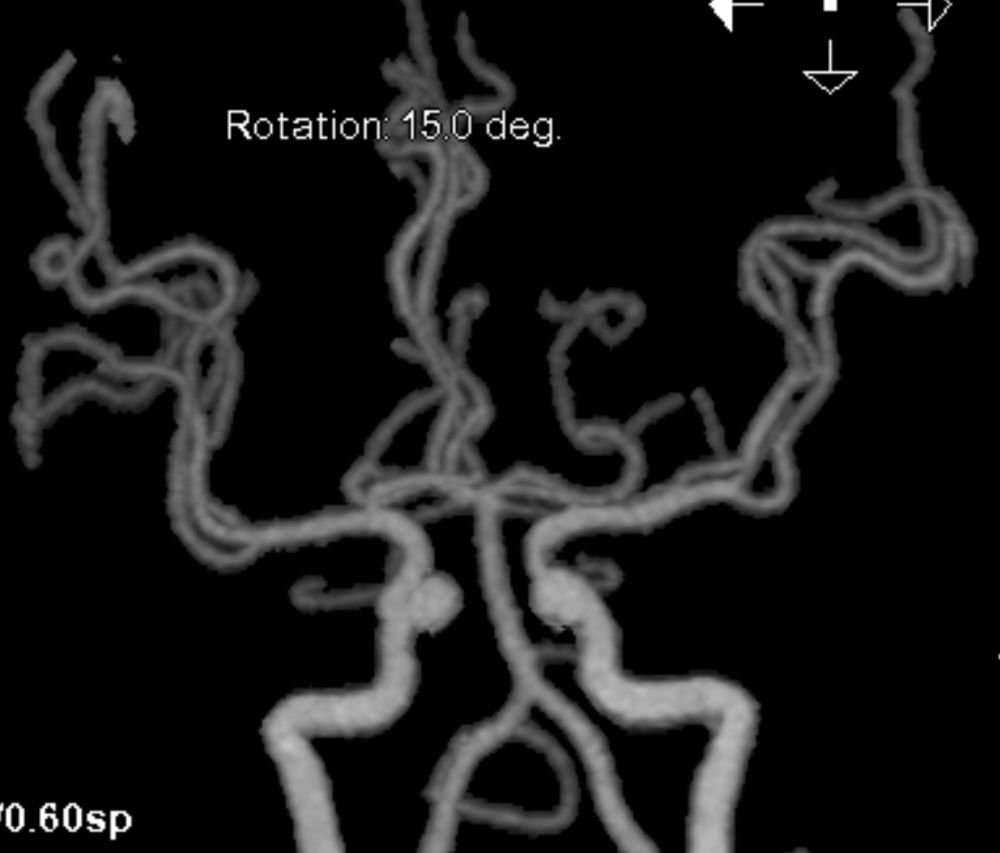

图2 CTA显示左侧大脑中动脉M1段闭塞

2.手术指征:患者应用阿替普酶溶栓后症状仍持续加重,CTA示左侧大脑中动脉闭塞。CTP存在CBF-CBV不匹配,有介入治疗指征。

患者取平卧位,全身麻醉成功后,右侧腹股沟区消毒铺无菌巾单,右侧股动脉行Seldinger穿刺,置入8F动脉鞘。150 cm泥鳅导丝携带5F单弯造影管超选进入左侧颈内动脉,造影显示左侧大脑中动脉M1段闭塞,M1及远端血管未见显影,患者左侧颈总动脉与主动脉弓成角较大,担心直接使用球囊导管到位困难,采取“长交换技术”,使用加硬超滑泥鳅导丝颈外支撑(260 cm,0.035),撤出单弯造影导管,8F Ewata球囊导引导管及5F 115 cm Navien中间导管沿加硬超滑泥鳅导丝到位,进一步导引入左侧颈内动脉,将Ewata球囊导管固定于LC1末段,接高压肝素盐水持续稳定滴注,路图引导下,送入Synchro微导丝(300 mm 0.014)及Rebar-27微导管组合,微导丝顺利通过大脑中动脉闭塞处,将微导管固定在LM2段上干,撤出微导丝,微量造影显示M1末段及以远显影,提示在真腔,撤出微导丝,沿Rebar-27将Reco取栓支架送入,当取栓支架与微导管末段Mark重合时,将微导管及支架撤到LM1段末段,固定支架导丝,缓慢撤出Rebar-27微导管,显示支架打开良好,手推造影,显示LM1段通畅,M1段远段及以远血管显影良好,等待5 min,再次手推造影,M1段远段及以远血管显影良好,此时应用等比例造影剂,将Ewata球囊导引导管远端球囊充盈,关闭滴注,中间导管内“冒烟”,显示造影剂滞留,用20 ml注射器,给予负压抽吸中间导管,同时回拉微导管及取栓支架,取出大量血栓。